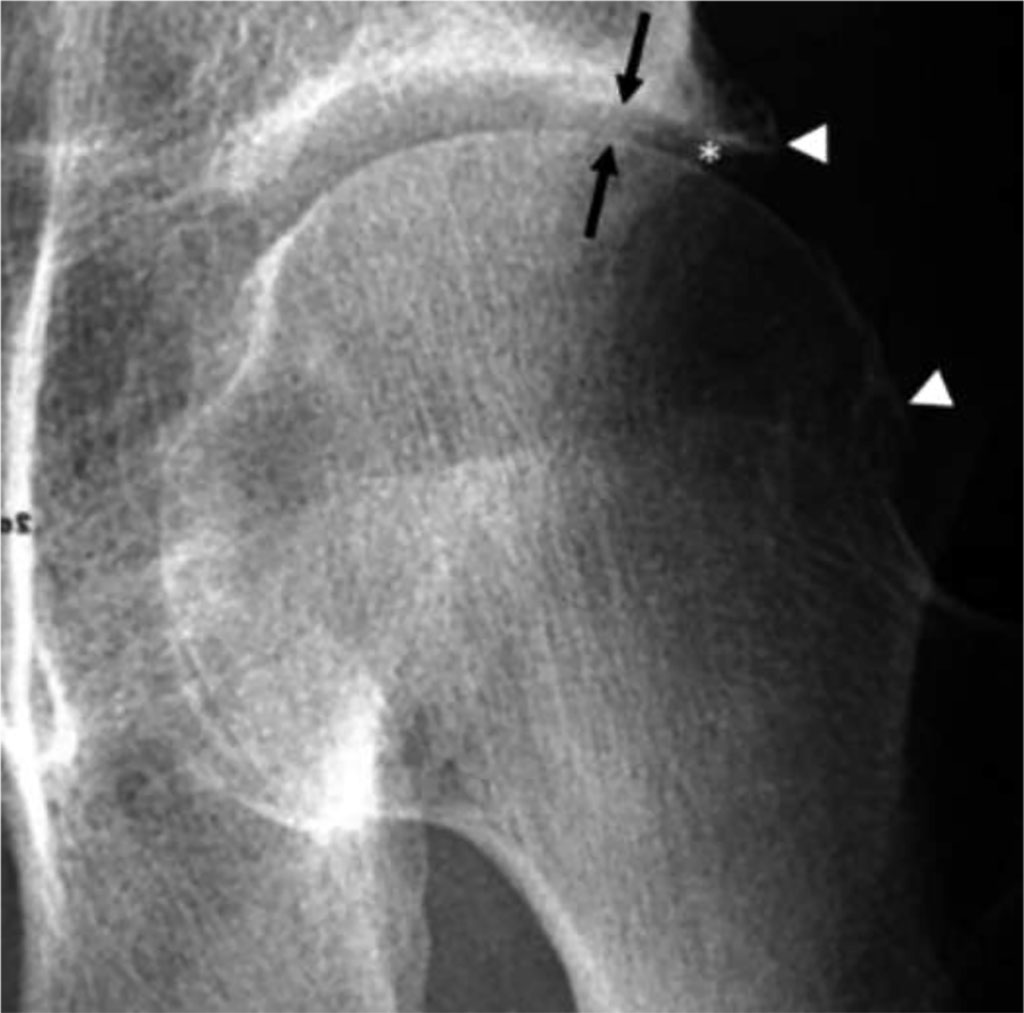

Degenerative joint disease is characterized by pain, which can be observed in tests such as flexion, extension, and internal rotation. Other symptoms include stiffness and decreased mobility, which make it difficult for the patient to perform daily activities. The etiology is associated with damage to the articular cartilage; disturbances in degradation and synthesis [5]. Studies show that risk factors for this disease include obesity, female gender, and age. It is believed that psychological disorders such as depression, anxiety disorders, and psychosis also play a role in the pathogenesis [6]. The diagnosis of degenerative joint disease of the hip is based on clinical symptoms and imaging tests. In the initial phase of the disease, magnetic resonance imaging (MRI) may be used to show changes in the articular cartilage. However, the most important imaging test for diagnosis is the anterior-posterior (AP) X-ray. Key to diagnosis is the narrowing of the joint space to below 2mm and the presence of osteophytes, which are bony outgrowths resulting from bone tissue overgrowth [7]. In treatment, rehabilitation, pain relievers, commonly NSAIDs, and surgical methods such as THA [8] or arthroscopy are used. Arthroscopy is an effective technique in treating femoroacetabular impingement (FAI) and rim injuries, which are one of the causes of degenerative hip joint disease [9].

Fig 2. Osteoarthritis of the left hip. AP RTG demonstrates lateral joint space narrowing (arrows) and marginal osteophytes (arrowheads) [7].